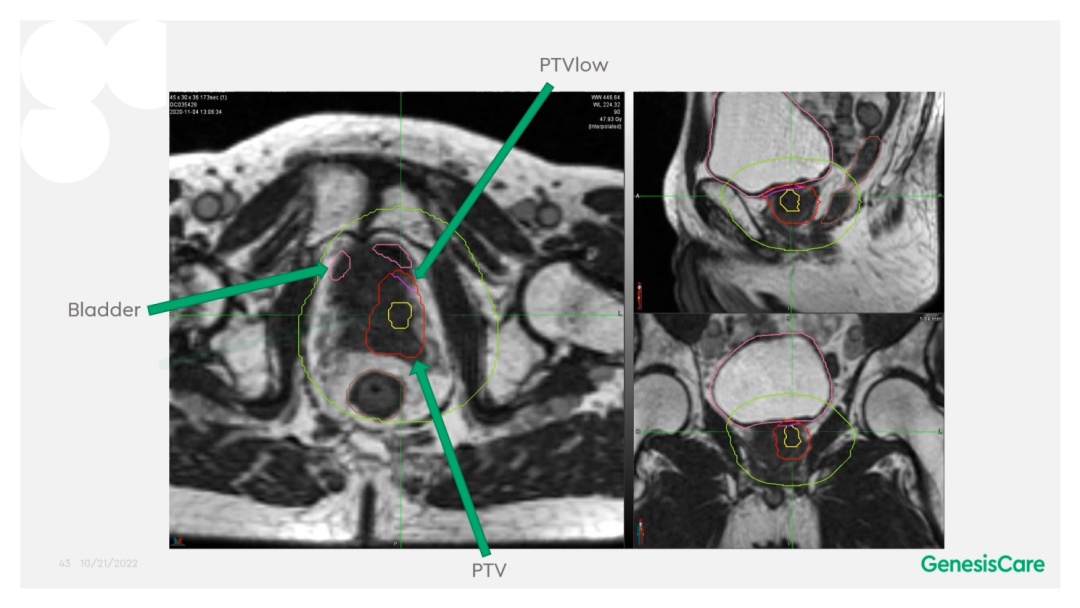

Dr. Camilleri表示,他们在做在线自适应放疗的时候,为了提高速度,仅对靶区外放3cm以内的危及器官的变化进行自适应调整或重新勾画轮廓,见Figure 13。这样可以缩短轮廓勾画的时间。对于放疗计划,使得95%的靶区体积接受到100%的处方剂量覆盖,并将最大剂量限制为2%的靶区体积不超过处方剂量的110%,这样就能保证在图像上很难显示的尿道不会超量,见Figure 14。另外,在制作放疗计划时,将PTV分为PTV LOW和PTV High,PTV和危及器官重叠的部分为PTV LOW,将PTV LOW的剂量目标设定在危及器官的耐受剂量以下,这样就能保证危及器官不超量,见Figure 15。